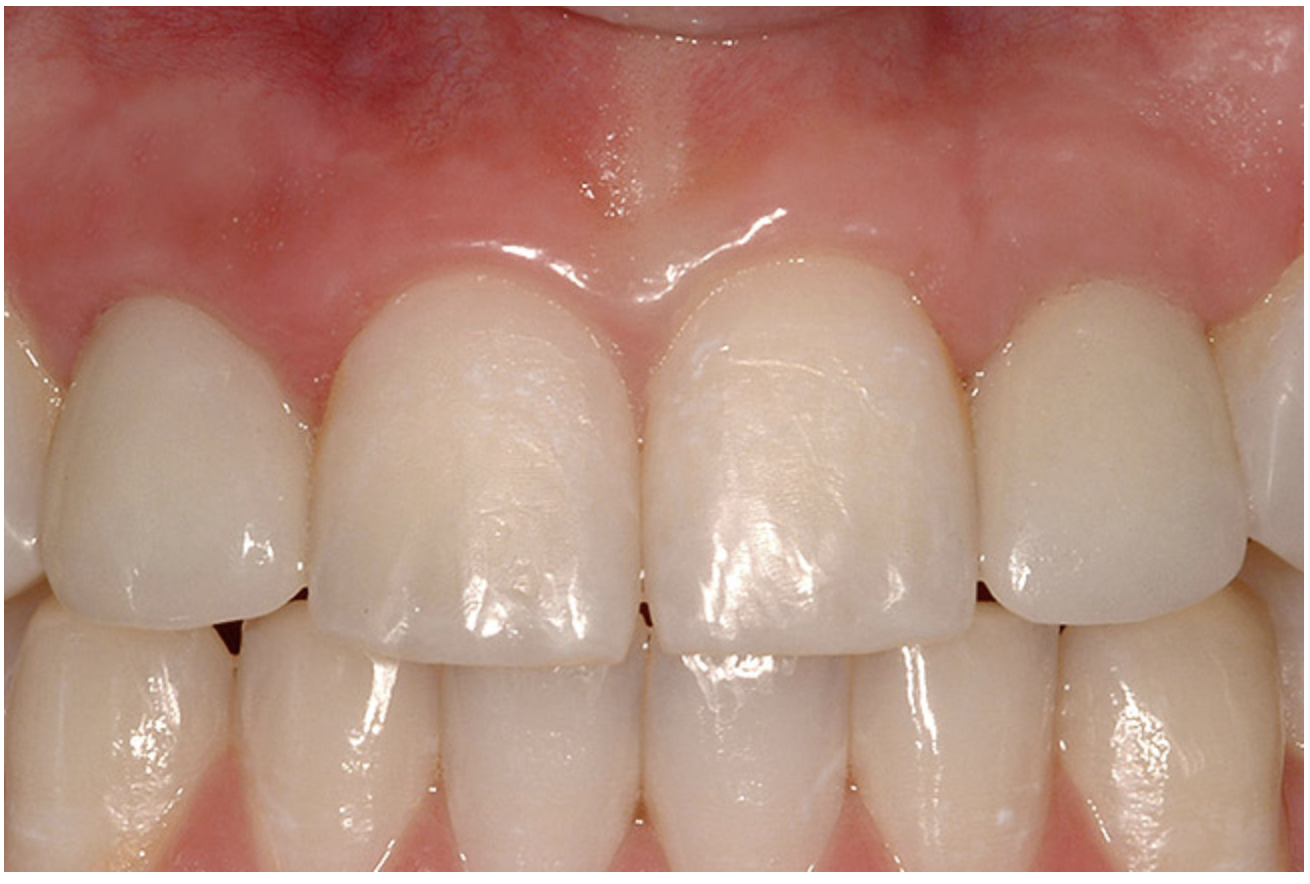

Before the day of surgery, the patient was seen by the orthodontist for the removal of the orthodontic brackets. The patient still was not pleased with the position of the two centrals, and it was determined that this would be addressed after implant placement (Figure 13A). The anatomical variations of the crestal tissue and lack of interdental papilla can be appreciated in the close-up views of the right and left sites (Figure 13B and 13C). There were no surprises on the day of surgery as all of the decisions were made during the planning phase, before the scalpel ever touched the patient. The occlusal view of the CT 3D model revealed the wider alveolar ridge on the right side and thinner crest on the left side (Figure 14A). This was confirmed when the full thickness mucoperiosteal flaps were elevated, and the underyling bone revealed (Figure 14B). The tooth-borne templates were designed to facilitate the drills and drilling sequence specific to the diameters of the predetermined implants (Figure 15A). Each template contained an embedded 5-mm long stainless steel tube, which was approximately 0.2-mm wider than each drill (just wide enough to allow for the drills to rotate freely). Once positioned over the natural teeth, the template was secure and offered precision accuracy in transferring the implant locations from the original software-designed plan, allowing the potential for internal and external irrigation (Figure 15B).

Figure 13a  Before implant surgery, the orthodontic brackets were removed, revealing (A) the position of the centrals, and (B, C) the anatomical variations of the crestal tissue and lack of interdental papilla.

Figure 13a

Figure 13b  Before implant surgery, the orthodontic brackets were removed, revealing (A) the position of the centrals, and (B, C) the anatomical variations of the crestal tissue and lack of interdental papilla.

Figure 13b

Figure 13c  Before implant surgery, the orthodontic brackets were removed, revealing (A) the position of the centrals, and (B, C) the anatomical variations of the crestal tissue and lack of interdental papilla.

Figure 13c